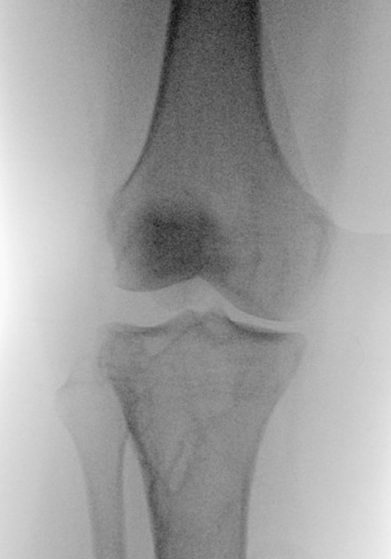

Diagnosing PLC injuries is made by a combination of medical history and physical examination of the knee. Diagnosis is often times confirmed by additional diagnostic imaging studies such as X-rays, MRI studies, and stress X-rays. As mentioned earlier, the PLC is often injured along with injuries to the PCL or ACL. It is important to recognize and diagnose PLC injuries when they occur with an ACL injury. A missed PLC injury can be the reason for ACL reconstruction failure when the ACL and PLC are both injured.